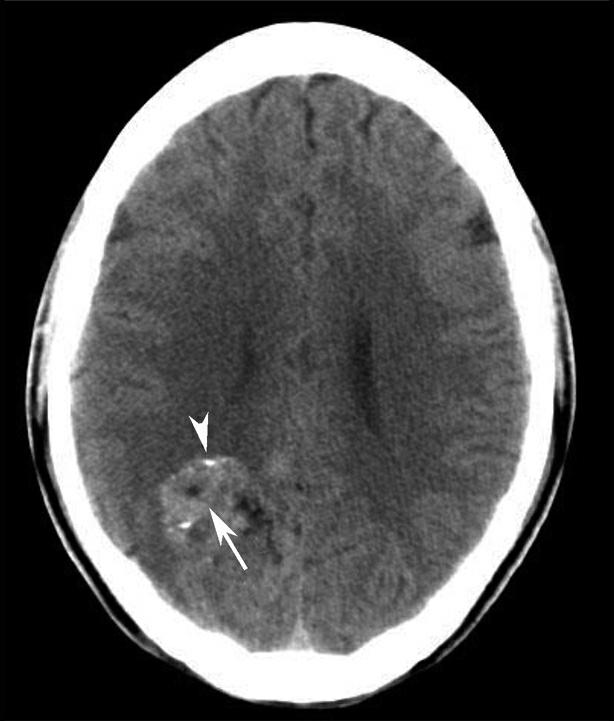

图1-2-87 脑挫裂伤并脑室内积血

右侧颞叶(白箭)、左侧基底节区(白箭头)大片状高、低混杂密度影。左侧侧脑室后角积血(黑箭)